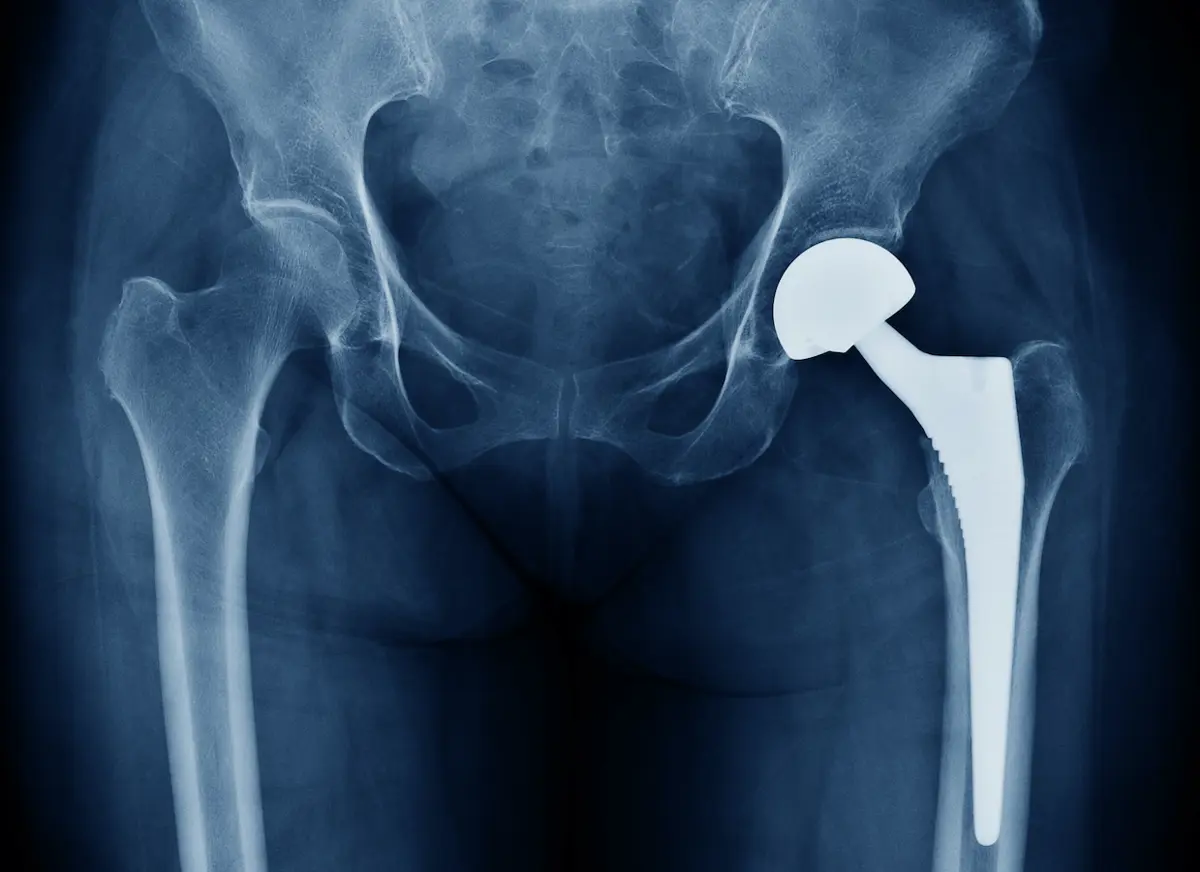

The International Consortium of Investigative Journalists (ICIJ) started releasing the Implant Files in late 2018. Their collection of investigative articles, researched by over 250 journalists worldwide, digs deep into the regulation of medical devices. Numerous examples of patient harm from across the globe paint a bleak picture of insufficient testing and regulation of medical devices, and of regulatory processes that are less than transparent and lend themselves to conflicts of interest. The category of devices includes anything that is placed inside the human body: breast implants, vaginal mesh, pacemakers, artificial hips, stents, heart valves, contraceptive devices, and so on.

Data from the US suggest that, in the last decade, around 80,000 deaths and 1.7 million injuries were possibly attributable to devices; in the European Union, with ‘light-touch’ regulation, there has been a steep rise in incident reports in recent years. The ICIJ summarises its findings as follows: “Patients around the world have become unwitting test subjects for new medical technology. Often following the trusted advice of their doctors, they have been injured, maimed and killed by poorly-tested implants.”

In their 2016 article “Pharmacovigilance is …vigilance”, Ralph Edwards and Rachida Soulaymani Bencheikh argue that medical devices are the proper concern of pharmacovigilance as much as medications; that the growing focus on individual patient welfare, alongside epidemiological perspectives, demands the adaptation of traditional methods and the development of new expertise. Many countries in the world rely on approvals in the US or Europe and have no local system for reporting device failures.

The ICIJ report makes it clear that the same stringent regulatory principles for medicines should also apply to medical devices and that there is an urgent need for reform.